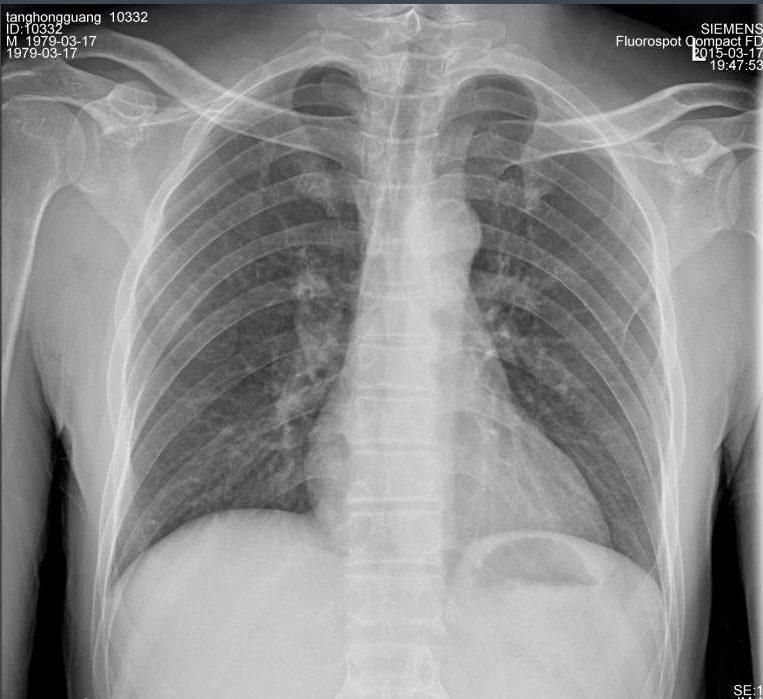

X射线,是一种频率极高,波长极短、能量很大的电磁波。具有穿透性,但人体组织间有密度和厚度的差异,当X射线透过人体不同组织时,被吸收的程度不同,经过显像处理后即可得到不同的影像。下面那米兰·(milan)中国官方来聊一聊关于X射线的三大特性分别是哪些。

X射线因其波长短,能量大,照在物质上时,仅一部分被物质所吸收,大部分经由原子间隙而透过,表现出很强的穿透能力。X射线穿透物质的能力与X射线光子的能量有关,X射线的波长越短,光子的能量越大,穿透力越强。X射线的穿透力也与物质密度有关,利用差别吸收这种性质可以把密度不同的物质区分开来 。

X射线同可见光一样能使胶片感光。胶片感光的强弱与X射线量成正比,当X射线通过人体时,因人体各组织的密度不同,对X射线量的吸收不同,胶片上所获得的感光度不同,从而获得X射线的影像  。